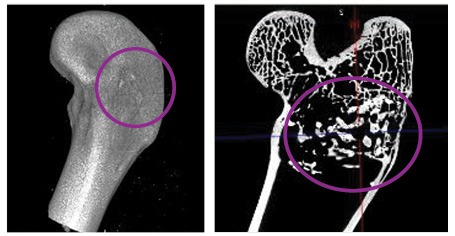

Standalone use in a trauma defect model showed excellent graft incorporation and remodeling **2**

trauma defect model_CT scan

Reconstructed µCT images of defects filled with standalone OssDsign Catalyst showing excellent graft incorporation (left) and remodeling (right).

2. Trauma defect pre-clinical lapine model. SIR2019-7; (Sept 2019) and SIR2019-8; April 2020 (data on file).